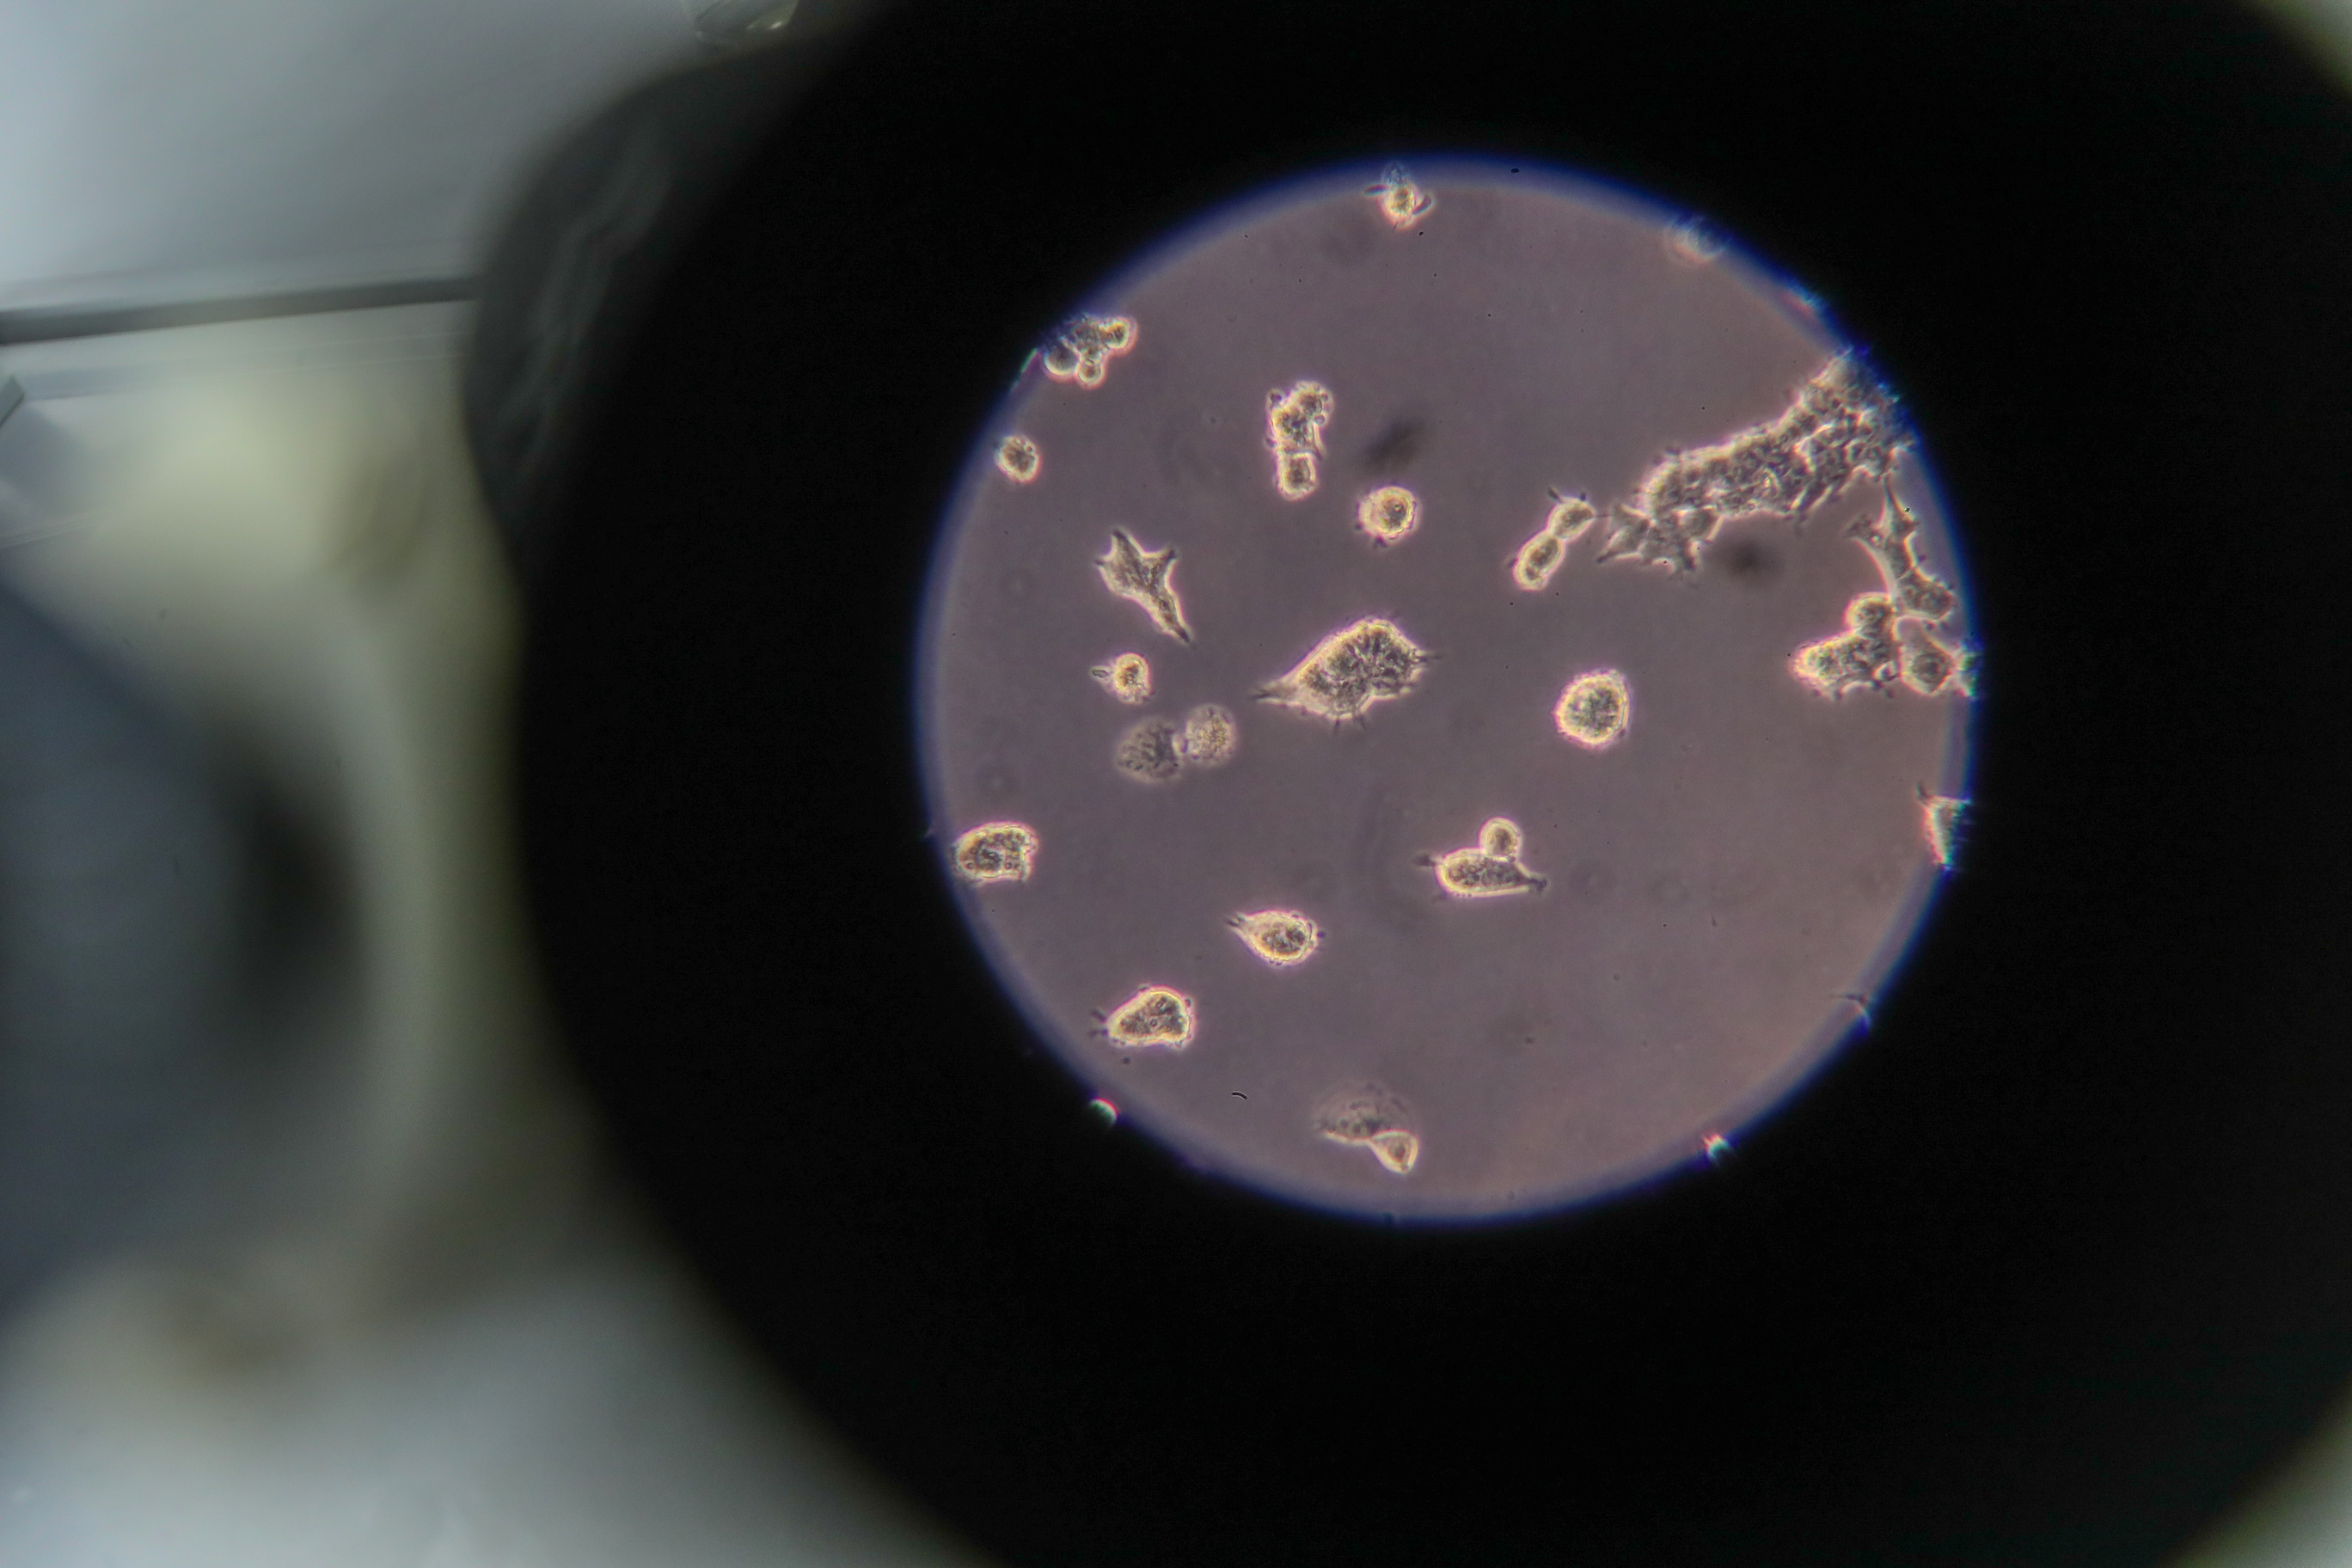

MOSCOW, December 22. /TASS/. The coronavirus strains circulating in Russia have no significant changes, and their analysis did not reveal any greater risks, Director General of the Vector State Research Center of Virology and Biotechnology Rinat Maksyutov said on Tuesday.

"Concerning those strains that we have analyzed, we are not talking about any greater risks of new coronavirus variants for humanity as a whole. We have detected over 1,400 different point mutations in Russian novel coronavirus isolates over the entire observation period, but most of them do not have any significant changes," he said in an interview broadcast by the Rossiya 24 TV channel.

According to Maksyutov, the novel coronavirus, just like any other virus, is changing all the time and accumulates its genetic changes. He noted that the Vector research center was studying the genetic changes of the novel coronavirus in Russia. "Every month, we receive novel coronavirus isolates from all regions across the nation. We pinpoint those changes, which accumulate in this pathogen," he explained.